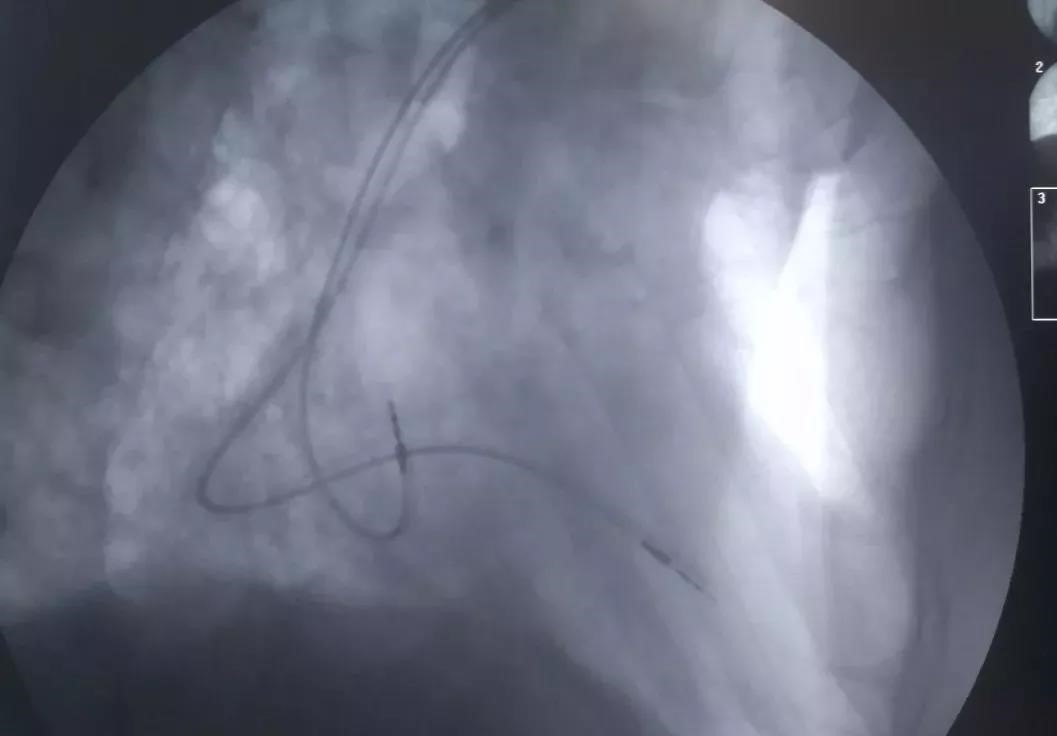

植入后电极位置